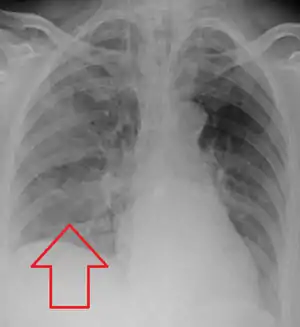

| Aspiration pneumonia in a ventilated person with a central line and nasogastric tube | |

Evaluation of aspiration is generally performed with a video fluoroscopic swallowing study involving radiologic evaluation of the swallowing mechanism via challenges with liquid and solid food consistencies. These studies allow for evaluation of penetration to the vocal folds and below but are not a sensitive and specific marker for aspiration.[15] Additionally, it is difficult to distinguish between aspiration pneumonia and aspiration pneumonitis.[16]

Aspiration pneumonia is typically diagnosed by a combination of clinical circumstances (people with risk factors for aspiration) and radiologic findings (an infiltrate in the proper location).[2] A chest x-ray is typically performed in cases where any pneumonia is suspected, including aspiration pneumonia.[17] Findings on chest x-ray supportive of aspiration pneumonia include localized consolidation depending on the patient's position when the aspiration occurred.[18] For example, people that are supine when they aspirate often develop consolidation in the right lower lobe of the lung.[18] Sputum cultures are not used for diagnosing aspiration pneumonia because of the high risk of contamination.[19] Clinical symptoms may also increase suspicion of aspiration pneumonia, including new difficulty breathing and fever after an aspiration event.[6] Likewise, physical exam findings such as altered breath sounds heard in the affected lung fields may also be suggestive of aspiration pneumonia.[6] Some cases of aspiration pneumonia are caused by aspiration of food particles or other particulate substances like pill fragments; these can be diagnosed by pathologists on lung biopsy specimens.[20]